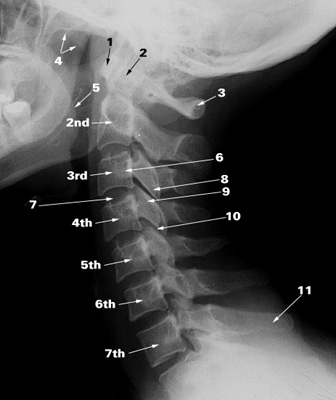

Advanced Neck: Aligning Cervical Vertebrae with Spinal Mechanics -- Marty Morales

Cervical Vertebrae

As massage therapists, when we work with the neck, our focus is generally  to decrease the hypertension in muscles and to decrease adhesions and fascial restrictions with the intent of improving the quality and quantity of neck mobility.  When we do this, we are potentially indirectly changing the alignment of the vertebrae, but we do so without specific goals of improving alignment, it is generally a bi-prodect of what we do.

In the Advanced Neck: Aligning Cervical Vertebrae with Spinal Mechanics class with Marty Morales, you willl learn how vertebrae move and how to affect the soft tissue around the cervical vertebrae to immediately improve the alignment of the cervical spine Marty Morales This, in combination with soft tissue work to support the improvement in vertebral alignment, will take your neck work a step further. For class details please click on the link below at:

• Oct 14-15 Advanced Neck: Aligning Cervical Vertebrae with Spinal Mechanics - 16 hours (Seattle)